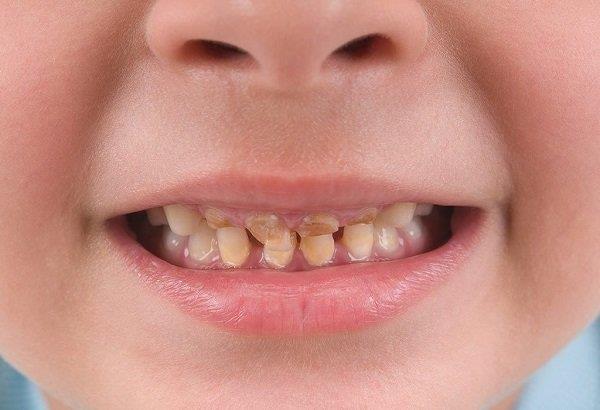

Yellow and discolored teeth in children: causes, treatment and prevention

Tooth discoloration is when the natural ivory white of a tooth turns a dark yellow, yellow-brown or opaque gray. Tooth discoloration can be: external discoloration or internal discoloration.

External discoloration may be temporary ; and can happen due to some drugs, foods, etc., On the other hand, internal discoloration can happen mainly due to underlying pathologies like metabolic disorders, enamel hypoplasia, etc.

The status of yellow teeth and discoloration

2.1. Caries

Your child can develop tooth decay due to bacterial activity in plaque. This can cause discoloration.